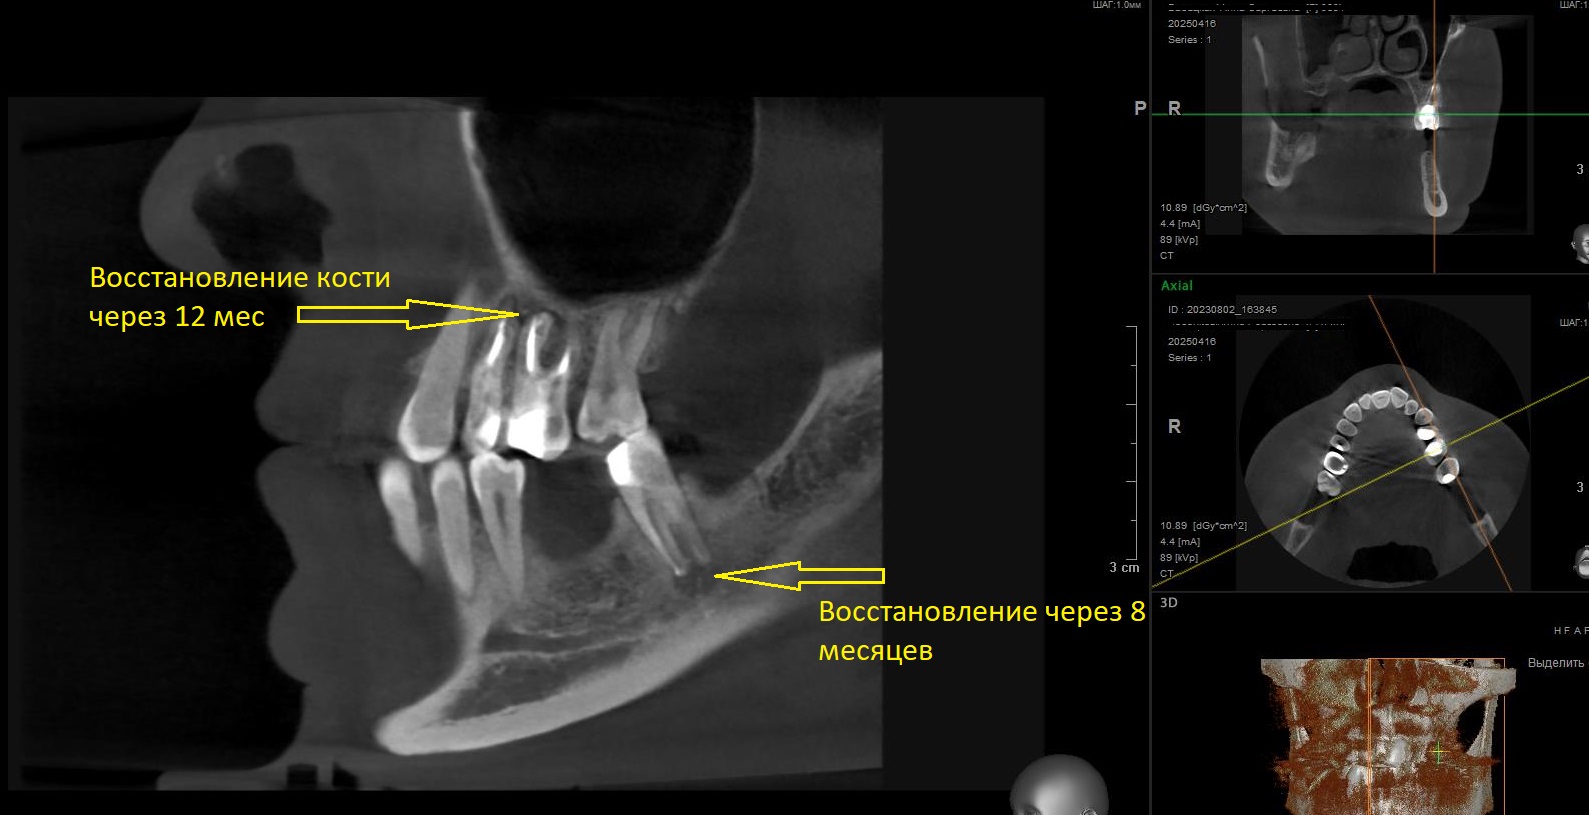

Нами было проведено повторное эндодонтическое лечение проблемных зубов.Через 6 месяцев видны отличные результаты заживления воспалительных изменений на верхушках корней, а также устранение воспаления в верхнечелюстной пазухе( гайморита).